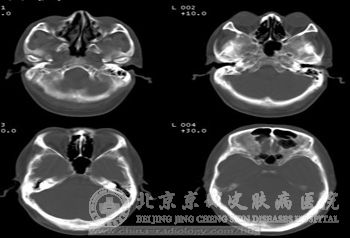

结节性硬化症除了皮肤症状外,还会累及神经系统,表现为癫痫发作及智力低下,这些也是此病的主要特征。一般在早期皮肤损害或颅内钙化前几年,癫痫就会发作,只是表现形式有所不同。初期时为婴儿痉挛症,接着会转化成全身性发作或部分性发作。

有些患者会有肢体瘫痪、共济失调、不自主动作等症状。少数病人会因室管膜下小结节阻塞脑脊液循环通路而造成脑积水以及颅内高压的现象。